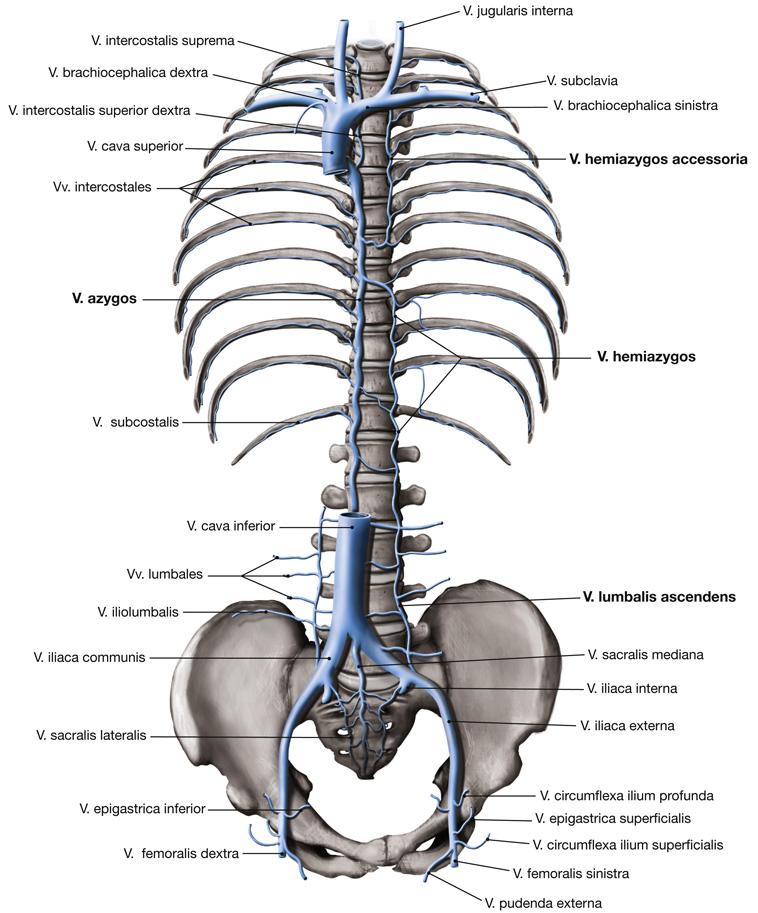

Fig 3.35: Vena cava inferior

atrium dextrum (RA) -

diaphragma

aorta -

v cava inferior